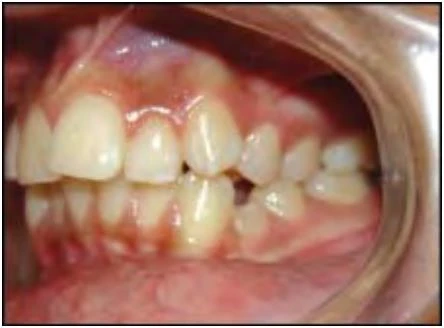

2.3 SAI KHỚP CẮN THEO MẶT PHẲNG NGANG

Trường hợp này bao gồm nhiều kiểu cắn chéo khác nhau. Thông thường các răng hàm trên nằm về phía ngoài so với các răng hàm dưới, nhưng đôi khi do cung răng hẹp hoặc vì một số lý do khác mà tương quan này bị xáo trộn. Chẳng hạn một hoặc nhiều răng hàm trên nằm về phía trong so với các răng hàm dưới, tình trạng này khác nhau về mức độ, vị trí và số lượng răng liên quan.